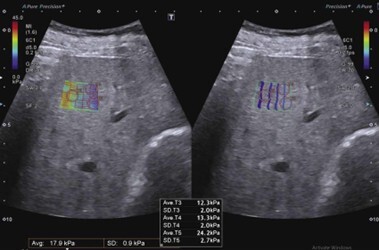

Elastografía Shear Wave: medición objetiva de fibrosis

La Shear Wave Elastrography (SWE) es el método principal para valorar fibrosis hepática.

¿Qué mide?

La rigidez del parénquima hepático, que aumenta a medida que progresa la fibrosis.

¿Cómo funciona?

- El transductor genera ondas de corte (shear waves).

- Se mide la velocidad de propagación.

- A mayor rigidez → mayor velocidad → mayor fibrosis.

Resultados

- Expresados en kilopascales (kPa).

- Permite estadificación F0–F4.

Utilidad clínica

- Hepatopatías crónicas

- Hepatitis virales

- MASLD

- Seguimiento evolutivo sin necesidad de biopsia

Ventajas

- Método no invasivo

- Reproducible

- Ideal para control longitudinal